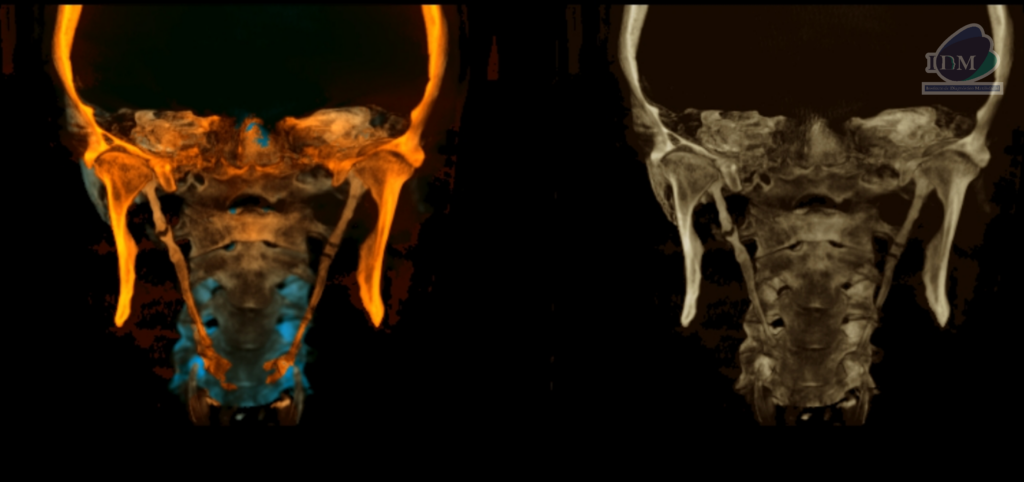

RECONSTRUCCIÓN 3D

Así mismo en la tomografía volumétrica de haz se confirma dicha mineralización, la cual se extiende desde base de cráneo hacia las astas menores del hueso hioides y presentado un patrón de mineralización pseudoarticulada.

- Mineralización bilateral de la cadena estilohioidea del tipo pseudoarticulada.